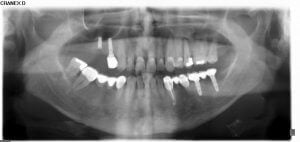

Kalıcı dişlerimiz çekildiğinde tedavi nasıl uygulanır? ...

İmplant ve estetik diş tedavileri ülkemizde kısa süre içerisinde hızlı bir şekilde uygulanması nedeni ile ...

İmplantın ömrü ve uzun süre kullanmak için yapılması gerekenler... ...

Tam dişsiz hastalar için implantlar büyük ölçüde çüpneme konforu sağlar ve yaşam kalitesini arttırırlar. ...

İmplant diş uygulanırken dikkat edilecek hususlar nelerdir? ...

İmplantın uzun ömürlü olması için iyi planlanması, iyi uygulanması ve iyi kullanılması gerekir. Temizliğinin ve ...